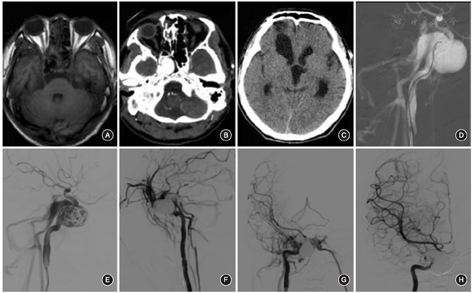

患者男,37岁,因颅底骨折致颅内感染3个月余入院。控制感染后,因急性脑积水行侧脑室-腹腔分流术。既往有鼻衄病史。患者自诉有颅内搏动性杂音。体格检查:右眼视力减退,眼前1米可数指,右侧瞳孔光反应迟钝,右侧眼球外展受限。行头颅MRI显示右侧海绵窦有一异常流空信号(图1A)。CT血管成像显示:双侧海绵窦呈异常染色,颈内动脉C4段可见巨大瘤样突起(图1B)。头颅CT显示双侧广泛额叶挫裂伤(图1C)。数字减影血管造影(DSA)提示右侧TCCF,其瘘口位于颈内动脉C4~C5段,血液向双侧岩上窦、岩下窦、大脑浅中静脉、蝶顶窦、海绵间窦等引流,右侧蝶窦和海绵窦内可见一巨大假性动脉瘤,大小约为22.5 mm×20.0 mm×18.0 mm(图1D)。明确诊断后,予手术治疗。全身麻醉下,患者取仰卧位,常规采用Seldinger法将6 F动脉鞘置入右侧股动脉。全身肝素后,首先经微导管(美国MicroVention公司)将14枚弹簧圈(美国Medtronic公司)置入动脉瘤瘤腔内,术中DSA显示瘘口和假性动脉瘤部分栓塞(图1E)。考虑继续予弹簧圈栓塞可能导致假性动脉瘤破裂,故注入Onyx-18胶,为防止Onyx-18胶经瘘口反流至颈内动脉,同时充盈球囊。经微导管缓慢、多次、少量注入Onyx-18胶约7.5 ml至海绵窦瘘内,直至假性动脉瘤达到完全栓塞(图1F,图1G)。由于瘘口变小,微导管难以通过颈内动脉,选择经右侧颈内静脉-岩下窦途径到达海绵窦内,然后充盈球囊保护颈内动脉,经微导管向瘘口处缓慢注入Onyx-18胶约7.5 ml,术后DSA显示病灶消失。出院时,患者的颅内杂音消失,双眼无结膜水肿。左、右瞳孔直径分别为2.5 mm和3.0 mm,右侧瞳孔光反应迟钝,右侧眼球外展轻度受限,其余活动正常,右眼的标准对数视力为4.3,左眼视力正常。其语言欠流利,存在情绪易波动和认知理解障碍,考虑与双侧广泛额叶挫裂伤有关。术后1年患者复查DSA显示病灶消失(图1H),右眼的标准对数视力恢复至4.8,双眼球活动正常,语言流利,认知理解力较前好转。